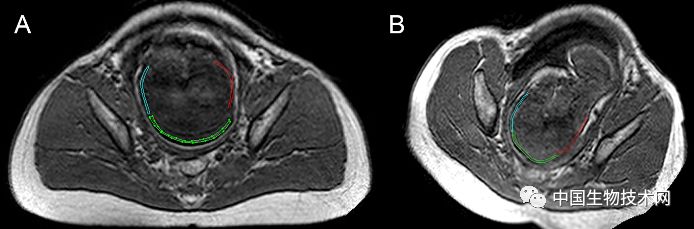

胎头成型和第二产程期间的头部形状变化 图片来源:《PLOS ONE》

近日,法国克莱蒙奥弗涅大学的研究人员利用三维磁共振成像(MRI)技术,拍摄了显示胎儿大脑和头骨在分娩前通过产道时如何改变形状的三维图像。该研究结果近日已发表在《PLOS ONE》上。

众所周知,胎儿头部在出生时是会发生形状改变的,这些变化被称为“胎头成型”,发生在分娩的第二阶段(第二产程)——当胎儿离开子宫通过产道时经历这些变化。然而,研究人员对胎头成型的细节仍知之甚少,只有一项先前的研究曾捕捉到这一过程的图像。

在这项新研究中,为了证明和描述胎头成型和分娩过程中大脑形状的变化,Olivier Ami博士领导的研究团队使用三维MRI捕捉了7名胎儿在分娩前和第二产程中头骨和大脑的详细图像。该分析揭示了所有7名胎儿在第二产程都有胎头成型,其中颅骨的不同部位存在不同程度地重叠。其中5名新生儿的头骨和大脑形状恢复到出生前的状态,但另外2名新生儿的头骨和大脑形状仍在变化。胎头成型程度最高的三名新生儿中有两名是通过紧急剖腹产手术分娩的,另一个是通过阴道分娩的。

图片来源:《PLOS ONE》

总的来说,该研究结果表明,胎儿在出生时承受的颅骨压力比之前所认为的要大,这可能是许多顺产新生儿出现无症状性脑出血和视网膜出血的潜在原因。

作者指出,还需要进行更大规模的研究以确认他们的发现,但这项工作证明了3D扫描技术在捕获胎头成型方面的价值。

Ami补充道:“在阴道分娩的过程中,胎儿的大脑形状会根据颅骨重叠的程度发生不同程度的变形。大多数新生儿出生后颅骨成型不再明显。有些头骨顺应变形以便于分娩,而另一些头骨不容易顺应变形。”